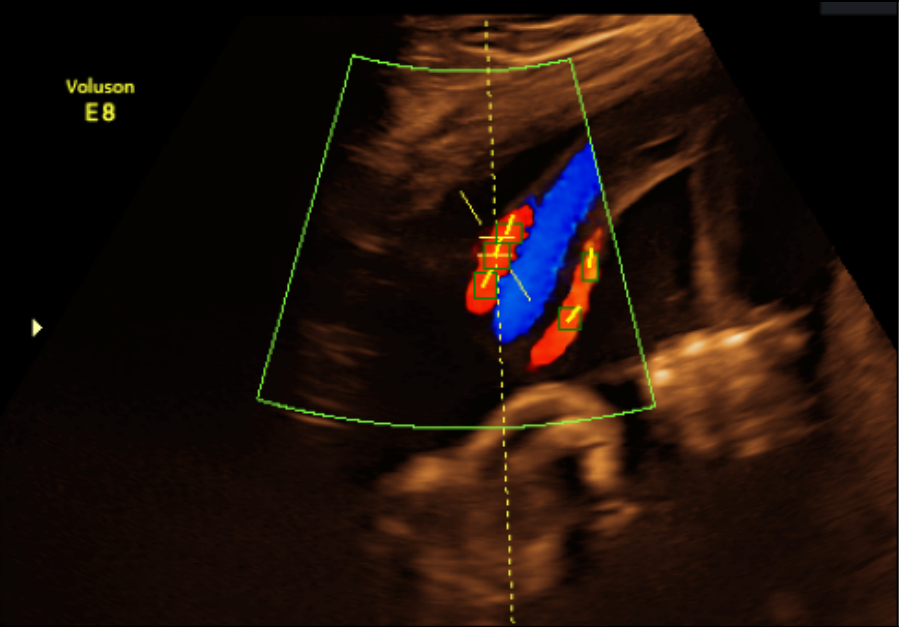

Refer to caption

(a) Expert annotated boxes and tangential lines

(b) Model predicted boxes and tangential lines

(c) Vectors pointing in direction of ultrasound source

Figure 4: Different stages in processing Color Doppler image.

Subsequently, the color Doppler images were annotated by a clinician using the open-source tool LabelMe [13]. On each image, regions corresponding to the correct anatomical site (i.e. the UA) were annotated with bounding box, which was done sparsely due to the inherent difficulty in annotating all correct anatomical sites with just bounding boxes. Finally, a tangential line going in the direction of the blood vessel were added on top of each annotated bounding box to indicate the vessel’s angle (see Fig. 4(a)).